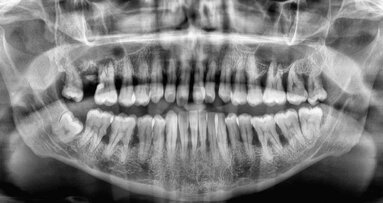

The dental structure most affected by radiotherapy is dentine, owing to its high organic content. Some of the alterations are caused by a process called radiolysis, leading to dehydration of the substrate, breakdown of the odontoblastic extensions and collagen fibrils, and cracks and fissures around the dentinal tubules. These alterations make the dental structure more susceptible to fracture and increase the dentinal roughness, which in turn affects the interaction between the substrate and microorganisms. Therefore, microbial colonisation, followed by the establishment of a more complex and structured biofilm, may occur. Bearing this in mind, endodontists need to redirect their treatment procedures regarding patients who have undergone radiotherapy in order to achieve endodontic success and restore oral health.